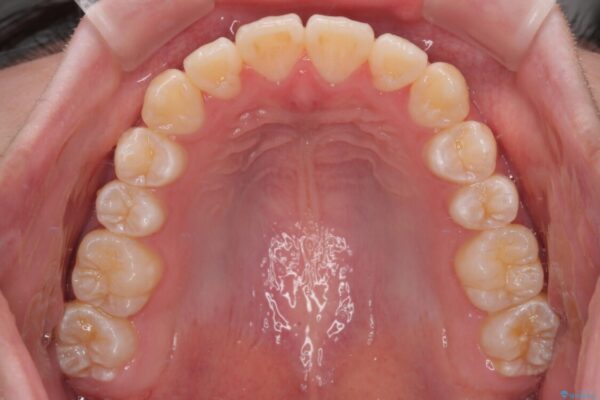

治療前

• 【モニター】前歯のデコボコをスッキリ解消!目立ちにくいワイヤー矯正でスピーディに治療完了 治療前画像

「前歯のデコボコ(叢生)をきれいに整えたい」とのことでご来院されました。